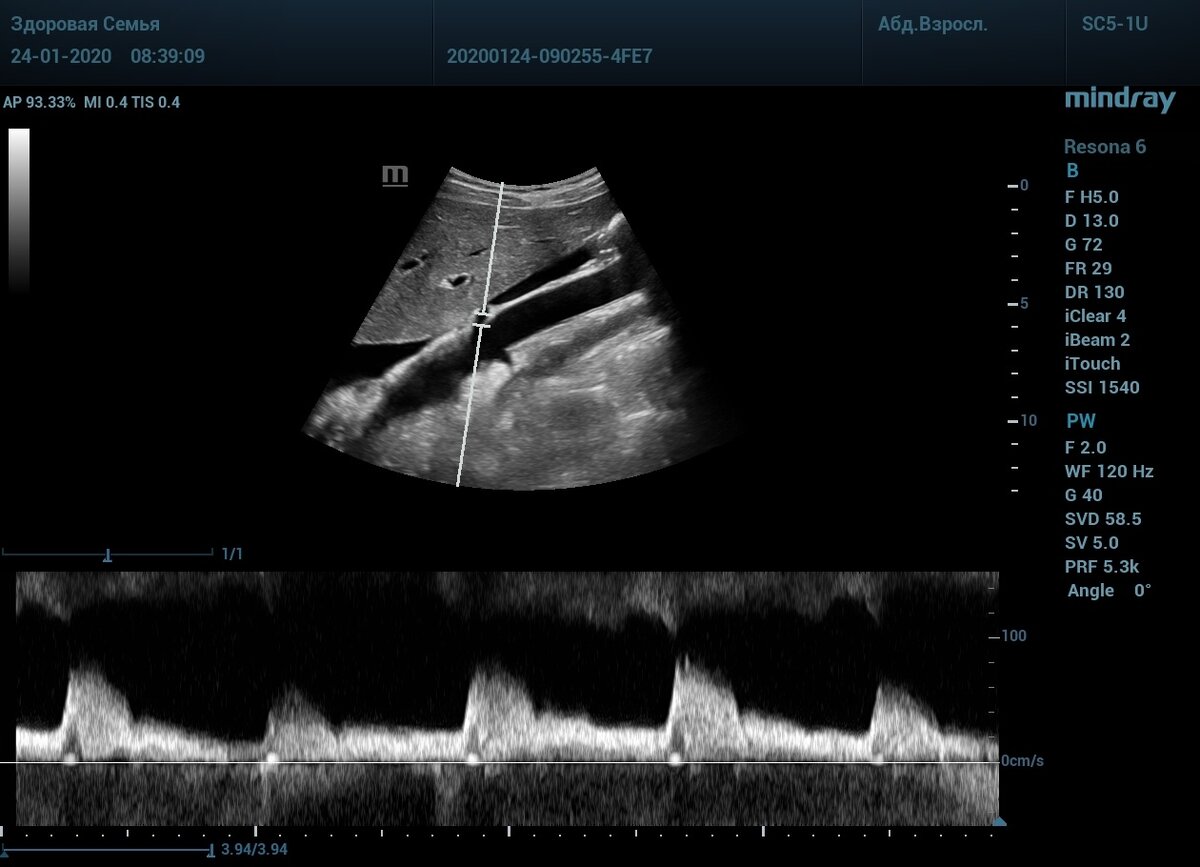

Истоки почечных артерий

🧐Сложной техникой считается получение продольного среза истока почечных артерий, того самого места где растут бляшки.

❕Требования: продольно аорта, почечные артерии как будто кожура банана отгибаются в стороны. Только так можно узнать истинную скорость кровотока в истоке.

➡️Стрелочками указаны истоки - кожура банана.